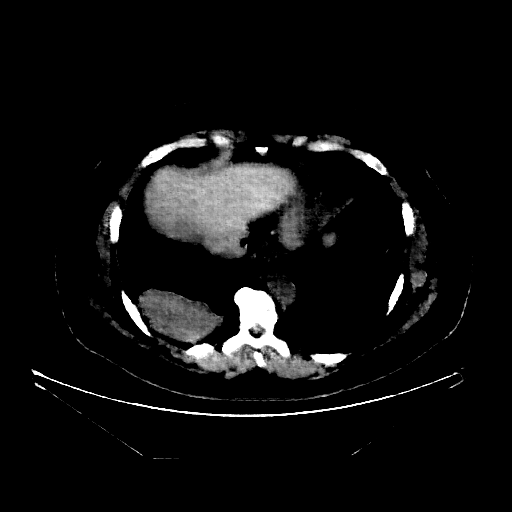

Reconstructed NATIVE CT scan (cycle consistency)

Full window (WL 1023.5, WW 4095 β†’ Low βˆ’1024, High +3071)

Lung window (WL -600, WW 1500 β†’ Low βˆ’1350, High +150)